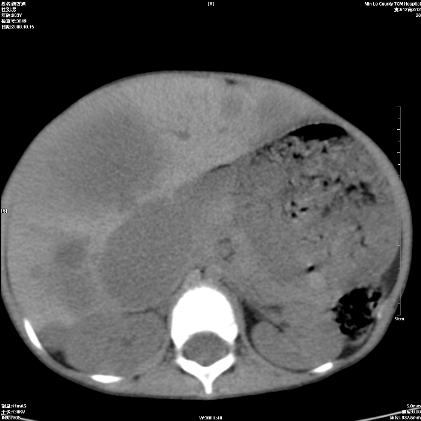

标题: PED1609:男性,3岁。彩超示肝Ca. [打印本页]

标题: PED1609:男性,3岁。彩超示肝Ca.

3岁;肝低密度灶;有钙化;有转移灶;考虑肝母细胞瘤;查afp

支持肝母细胞瘤肝内转移

考虑神经母细胞瘤并肝转移

考虑:1、右侧后下纵隔畸胎瘤。

2、肝脏多发血管内皮细胞瘤。

建议:增强确诊。